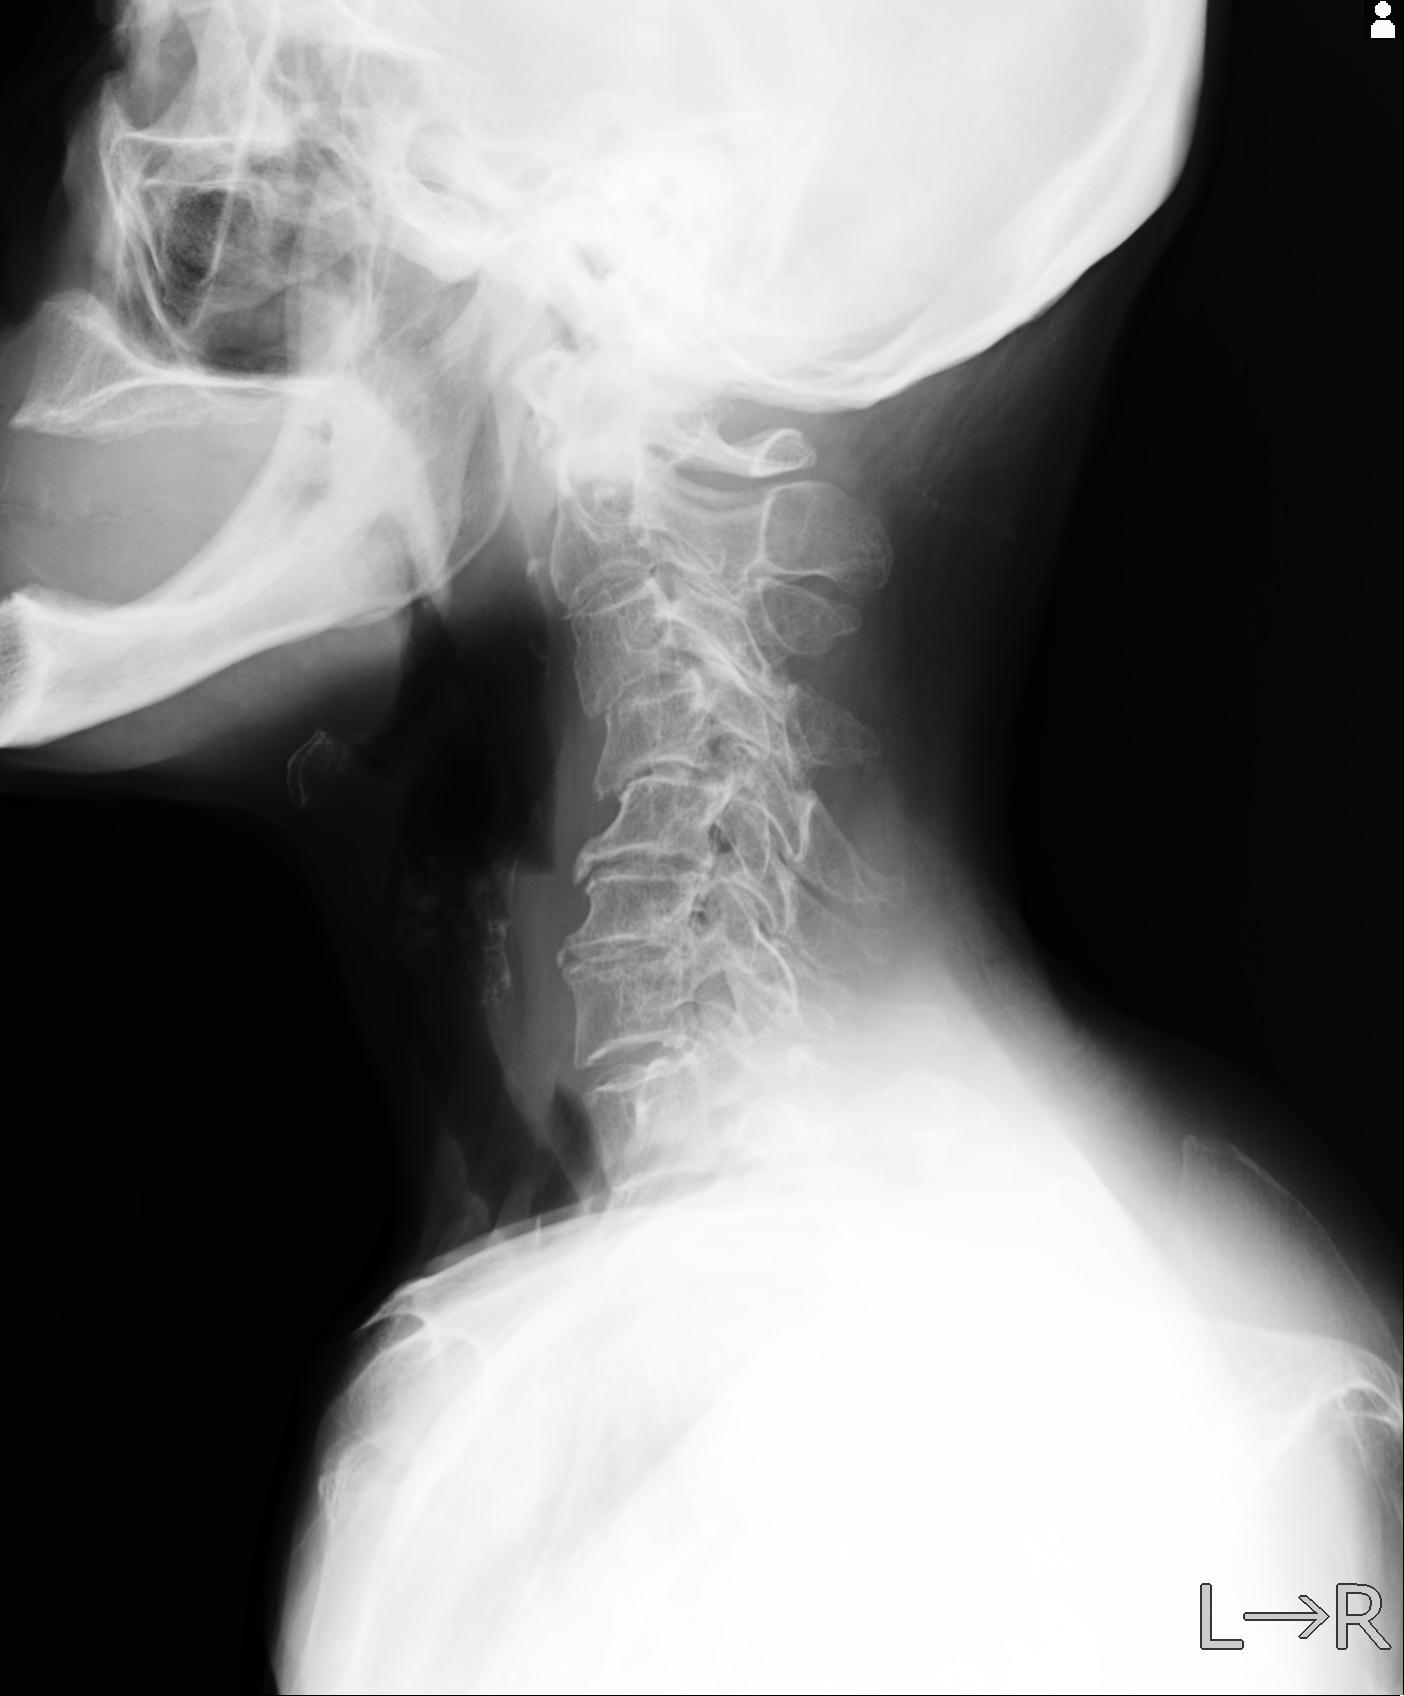

102916 2/1 と 3/22 腰椎 2R 74歳女性 LIFX